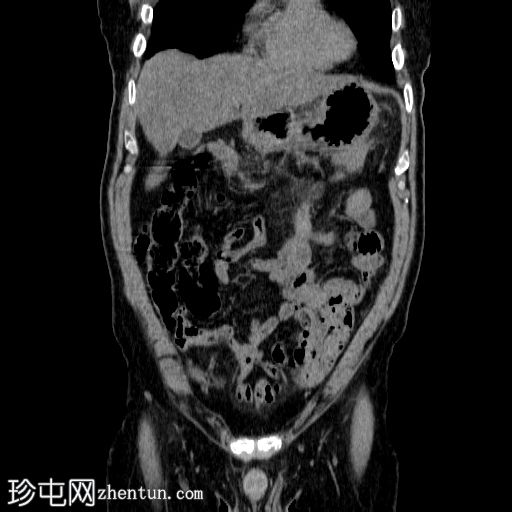

冠状面

非造影

胰体尾弥漫性增大,特征为胰腺实质低强化,无明显坏死区域。

胰周筋膜平面边界不清的污迹,无明显壁形成、气室、固体碎片或血液产物。

多个亚厘米大小、非特异性的腹主动脉旁淋巴结和肠系膜淋巴结,可能具有反应性。

病变横向延伸至左前肾旁间隙,伴有Gerota筋膜增厚。

病变向下延伸至盆腔。

无肠系膜或脾脏血管阻塞的证据。

未见导管扩张或钙化。